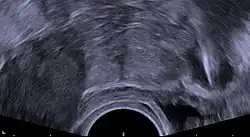

Regardless of the IUD type, some potential side effects are similar for all IUDs. Some of these side effects include bleeding pattern changes, expulsion, and pelvic inflammatory disease (especially in the first 21 days after insertion). The occurrence of IUD migration is rare, with reported rates in medical literature varying between 0.1% and 0.9%. However, when migration occurs, it can lead to serious complications such as uterine perforation and, in rare cases, bladder perforation. Bladder perforation, while uncommon (affecting only 2% of displaced IUDs), can result in symptoms like urinary frequency, hematuria, and stone formation, often necessitating surgical intervention for removal.[82] Regular monitoring and imaging, such as ultrasound or CT scans, are recommended to detect such complications early and ensure timely treatment. A small probability of pregnancy remains after IUD insertion, and when it occurs, there is a greater risk of ectopic pregnancy.[83]